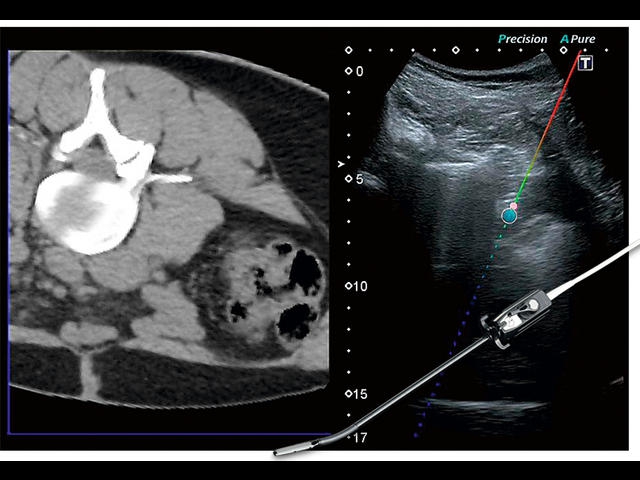

Aplio 500 – ультразвуковой сканер премиум класса, сочетающий в себе быстродействие диагностики и отличное качество визуализации. Более 30 датчиков на выбор, в т.ч. матричные, монокристаллические, 4D, эндоскопические для любых типов исследований. Ультразвуковой сканер позволяет изучать анатомические структуры в высоком разрешении.

Обновленная версия легендарного УЗ-сканера. Стационарный аппарат экспертного класса Aplio 500 Toshiba NEW, визуализирует анатомические структуры в высоком разрешении. Модель позволяет выявить микрокальцификаты, новообразования, нарушения в работе сердца, сосудов и мышц. Присутствует функция виртуальной эндоскопии, 4D-сканирования, эластометрии тканей, УЗИ с контрастированием. За повышение качества изображения отвечают технологии ApliPure и Superb Microvascular Imaging. Первая задействует возможности пространственного и частотного кодирования, формирует цельный визуальный ряд с сохранением клинических маркеров. Вторая улучшает отображение микрососудистого русла, используя доплеровский эффект. Модель оснащена 21-дюймовым монитором, имеет 4 активных порта. Возможно подключение педиатрических, интраоперационных, лапароскопических и чреспищеводных датчиков.

IFusion: